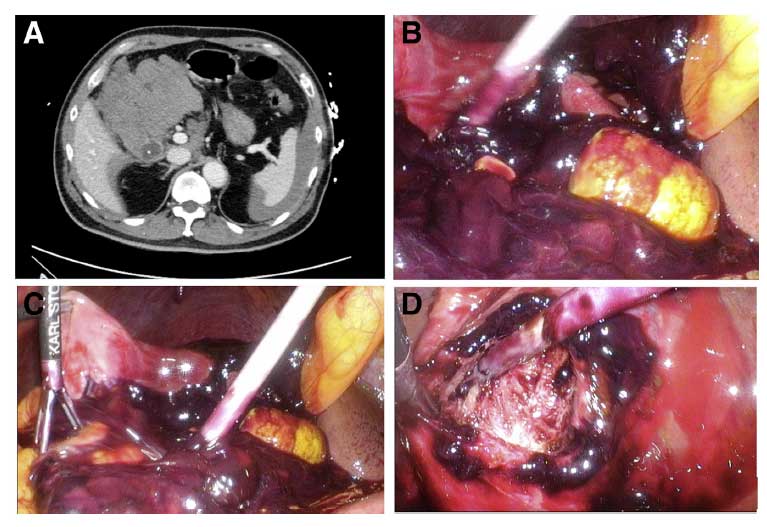

QUIZ: Uma causa rara de hemoperitônio